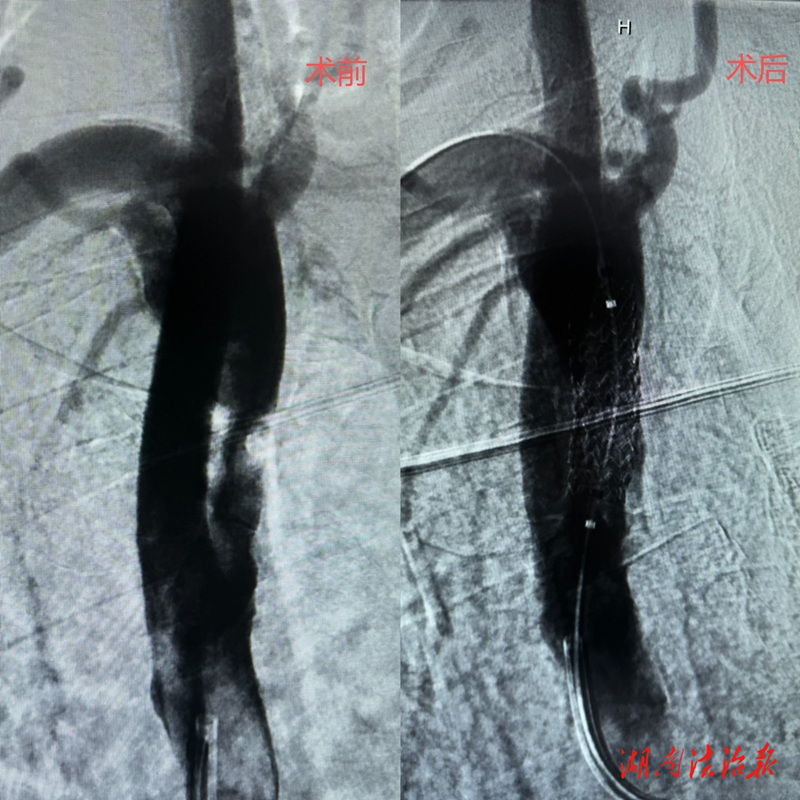

本次手术患者为74岁男性,因脑梗死入住该院中风科。入院后,科室团队详细问诊查体、完善各项检查,经数字减影血管造影(DSA)确诊:右侧锁骨下动脉起始部重度狭窄,狭窄程度超 90%,合并锁骨下动脉盗血综合征。该病症若延误治疗,极易诱发再次脑梗死、上肢缺血性坏死,严重危及生命,具备明确手术指征。

结合患者高龄、基础身体条件、血管病变位置与狭窄程度,科室团队全面评估手术风险与获益,经多次病例研讨、精准制定手术方案,最终确定采用微创介入手术治疗。该术式无需外科开胸开刀,仅通过股动脉穿刺建立微小通道,在 DSA实时影像引导下,将介入器械精准送达病变血管,先行球囊扩张开通狭窄血管,再植入支架支撑血管壁、重建正常血流,具备创伤小、出血少、术后恢复快、并发症少的显著优势。

手术过程精准顺畅,介入团队娴熟运用球囊穿梭、特洛伊木马等先进介入技术,顺利完成股动脉穿刺、导丝导管通行、球囊预扩张、支架精准输送定位与释放全部操作。术中实时造影显示,患者狭窄血管完全开通,支架位置精准、血管壁贴合良好,脑部及上肢血流恢复通畅,盗血现象即刻消除,双侧上肢血压恢复对称,手术全程顺利完成。